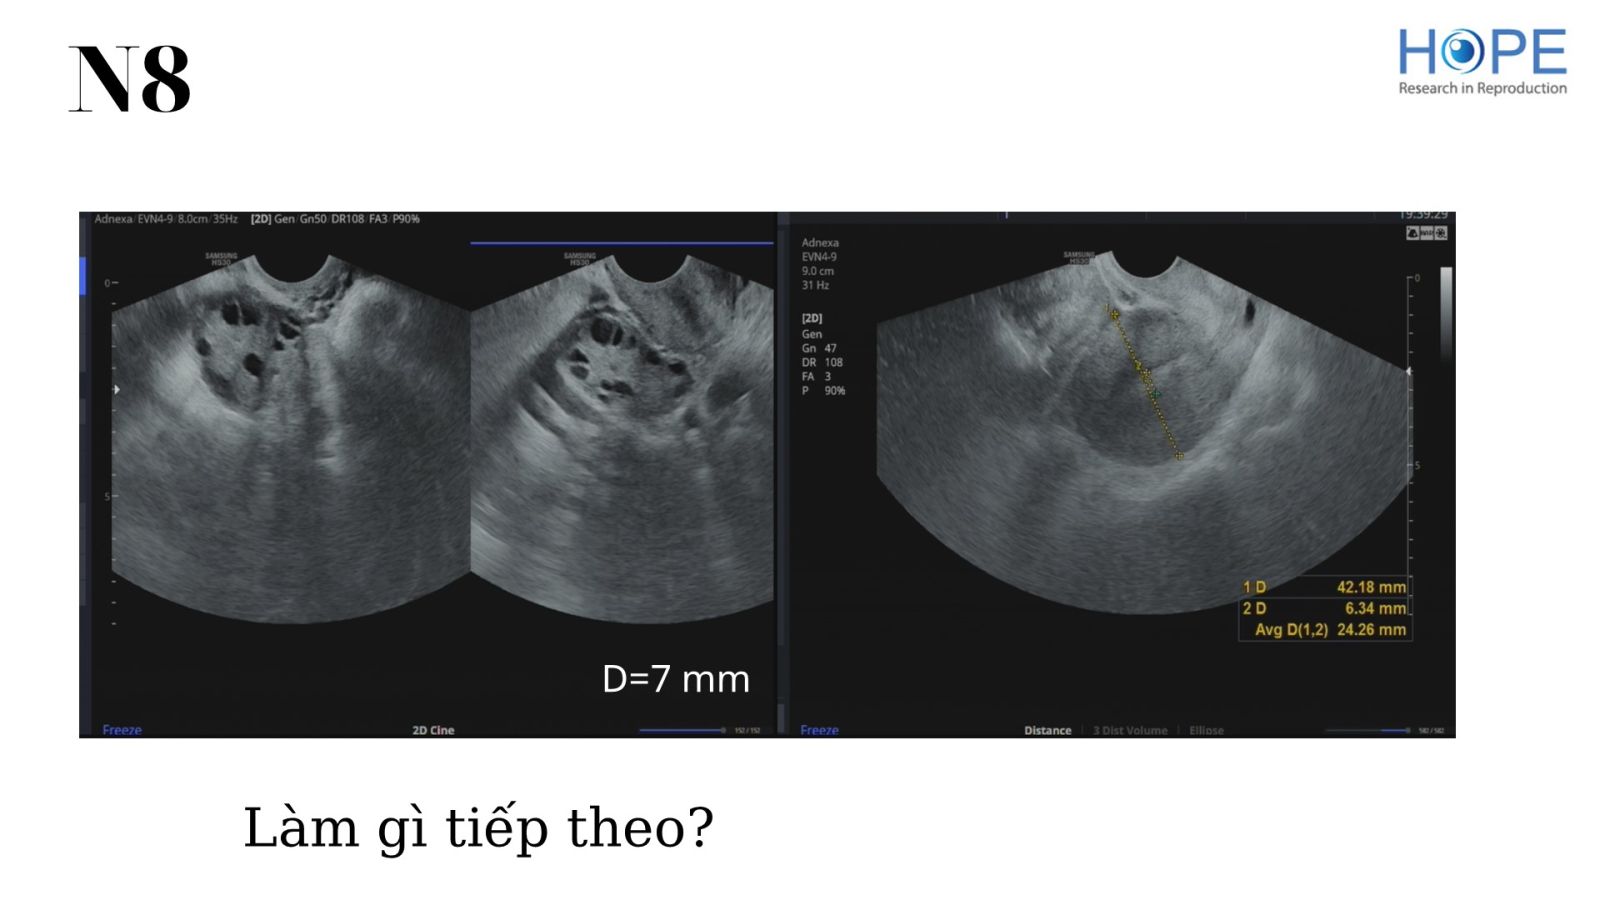

Các phác đồ kích thích buồng trứng nhẹ để IUI –  cách theo dõi kích thích buồng trứng

BS Lê Thị Hà Xuyên - IVFMD Phú Nhuận